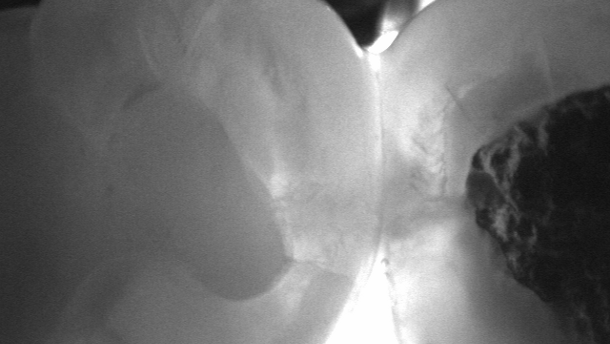

Visual examination is still the most important method for detecting carious lesions easily and quickly. Nevertheless, visual diagnosis has its weaknesses, especially in the approximal area. Therefore, additional aids are required, such as bitewings, which have become the gold standard in this field. More recently, near-infrared transillumination has become a new method for reliable and X-ray-free caries detection.

In the webinar, Dr Jan Kühnisch, a research fellow at the Department of Conservative Dentistry and Periodontology at the University of Munich, will report on the potential of the method, his own research results and previous clinical experiences with near-infrared transillumination. Furthermore, he will compare the method to established techniques and describe typical treatment strategies for different caries stages.

The one-hour webinar, titled “Early detection of carious lesions with X-rayfree near-infrared transillumination and appropriate treatment”, will be broadcast live online on 25 March from 2 p.m. BST. Participants will be able to ask questions via a chat window and have the opportunity to earn a continuing education credit by completing a multiple-choice questionnaire on the topic discussed.